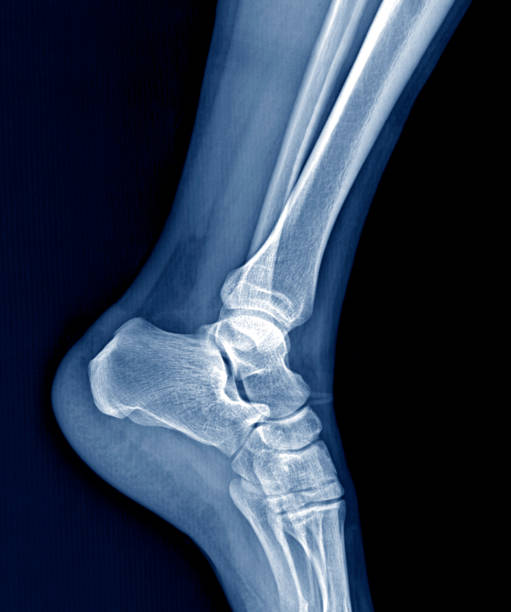

발뒤꿈치 통증의 다섯 번째 원인은 발목 터널 증후군입니다. 내복사(medial malleolus)와 종골(calcaneus) 사이의 족근관(tarsal canal)을 지나는 후경골신경(posterior tibial nerve)이 눌리거나 손상되면 저림과 화끈거리는 증상이 나타날 수 있습니다. 이때의 통증은 신경압박에 의한 것으로 위에서 언급한 여러 증상과 다르게 통증의 위치가 명확하지 않고 신경통로를 따라 퍼지는 특징을 가지고 있어 치료가 조금 더 어려운 증상입니다.